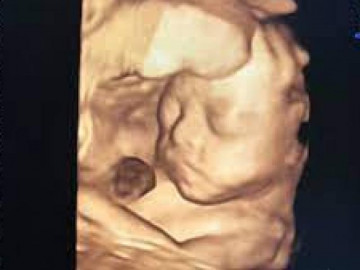

Thai nhi 19 tuần

Thai nhi tuần thứ 19 đã có thể nghe được âm thanh từ bên ngoài bụng mẹ.

Tuần 19: Mít yêu đã bằng quả xoài